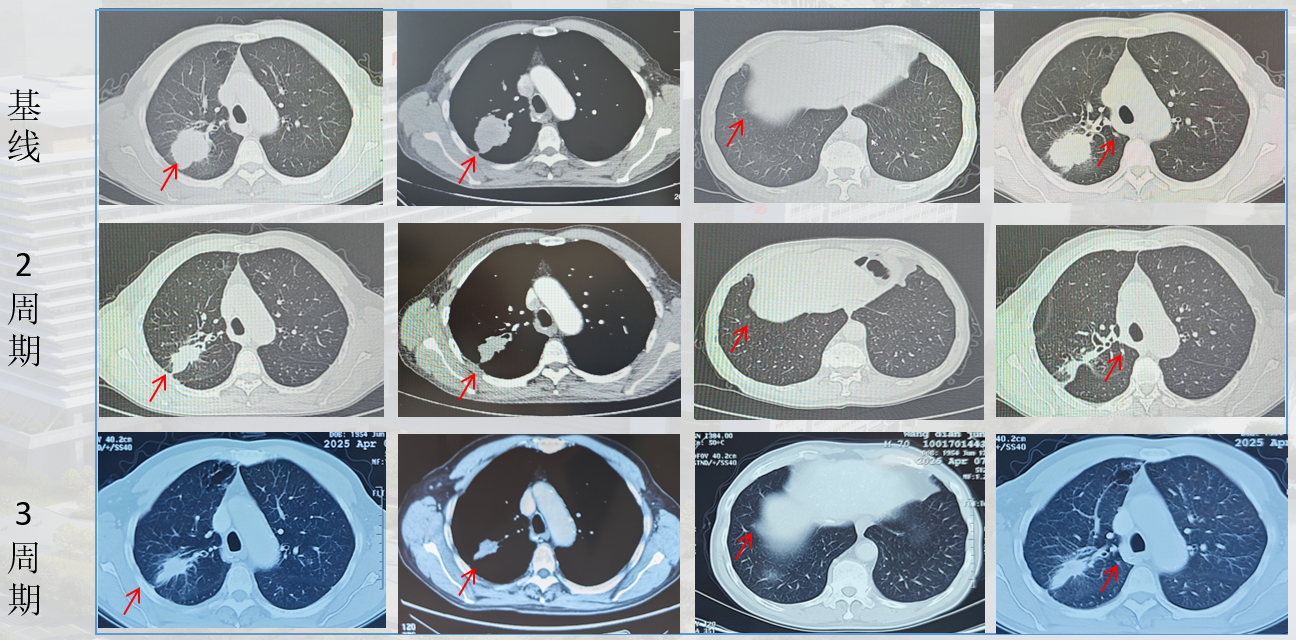

1、2025.01新辅助治疗:纳武利尤单抗360mg Q3W+培美曲塞+顺铂 Q3W;3周期。

术后诊断:右肺上叶恶性肿瘤术后(腺癌);ypT1aN0M0 Ia1期 ;ECOG 1分。

在治疗层面,基于MDT讨论,本病例采用了“新辅助免疫联合化疗→手术→术后辅助免疫”的全程管理模式。治疗结局显著验证了该策略的有效性:术后病理评估显示肿瘤病理学缓解率达99%,接近pCR,并成功实现从cT2bN0M0至ypT1aN0M0的病理学降期。该结果提示患者有望获得长期无病生存。本案例有力证实了该联合治疗模式在局部晚期非小细胞肺癌(NSCLC)患者中具有重要临床应用潜力,也为未来临床实践与研究方向的拓展提供了有益借鉴:

新辅助免疫联合化疗、后续手术加辅助免疫的围术期全程管理模式,其有效性和安全性已在大型III期临床试验中得到验证。关键性的CheckMate-77T研究证实,对于可切除的II-IIIB期NSCLC患者,与单纯化疗相比,纳武利尤单抗围术期方案(新辅助纳武利尤单抗+化疗,序贯术后纳武利尤单抗辅助治疗)显著改善了患者的无事件生存期(EFS),并大幅提高了病理完全缓解(pCR)率。 该研究结果表明,围术期方案可显著降低42%的疾病复发、进展或死亡风险,pCR率更是从化疗组的4.7%跃升至纳武利尤单抗组的25.3%。 本例患者高达99%的病理缓解率,正是这一卓越疗效在真实世界病例中的有力印证。